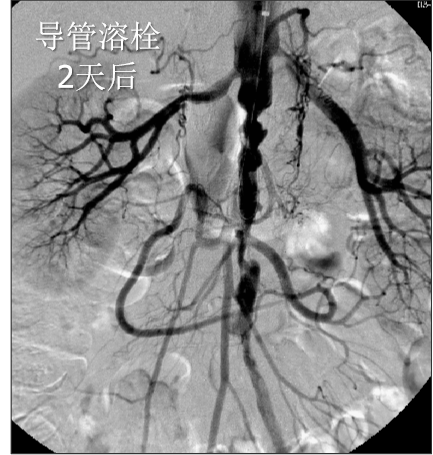

男性、58岁,间跛100米、慢性下肢缺血,病史3年

造影提示患者为长段闭塞,如果一期行腔内治疗,则累及肾动脉;所以行预置导管溶栓,后行支架术,血流重建效果显著。